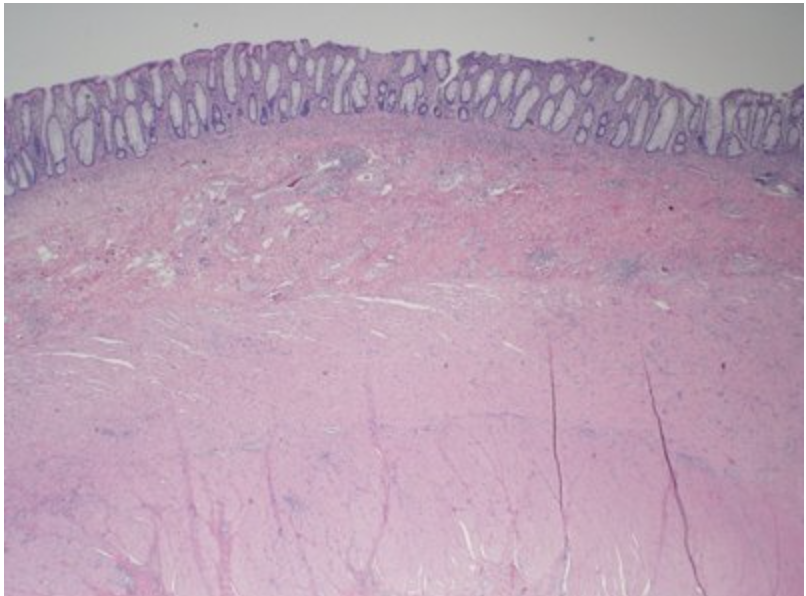

In this image, identify the component responsible for absorption and secretion!

This is a picture of a colon. The correct answer is the epithelium which lines the lumen of the colon. Remember that in the human body, the epithelial tissue’s functions include secretion, absorption and/or protection.